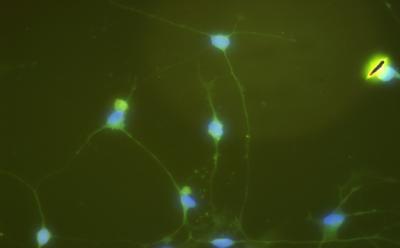

To date, it remains poorly understood whether astrocytes can be easily reprogrammed into neurons. Mash1 and Brn2 have been previously shown to cooperate to reprogram fibroblasts into neurons. Dr. Yongjun Wang and team from Shanghai University of Traditional Chinese Medicine in China found that and found that Brn2 was expressed in astrocytes from 2-month-old Sprague-Dawley rats, but Mash1 was not detectable. Thus, the researchers hypothesized that Mash1 alone could be used to reprogram astrocytes into neurons. Murine stem cell virus (MSCV)-Mash1 recombinant plasmid was constructed and transfected into GP2-293t cells to produce retrovirus. One week later, the changes in morphology of astrocytes were detectable, which showed typical neuronal characteristics. Moreover, β-tubulin expression levels were significantly higher in astrocytes expressing Mash1 than in control cells. These results, published in the Neural Regeneration Research (Vol. 9, No. 1, 2014), indicate that Mash1 alone can reprogram astrocytes into neurons. This method determined an easier process of reprogramming through the endogenous expression of important transcription factors, which avoids malignant transformation due to the spontaneous reactivation of viral transgenes.

Article: " Mash1 efficiently reprograms rat astrocytes into neurons" by Daofang Ding1, 2, Leqin Xu1, 2, Hao Xu1, 2, Xiaofeng Li1, 2, Qianqian Liang1, 2, Yongjian Zhao1, 2, Yongjun Wang1, 2 (1 Institute of Spine, Shanghai University of Traditional Chinese Medicine, Shanghai, China; 2 Longhua Hospital, Shanghai University of Traditional Chinese Medicine, Shanghai, China)